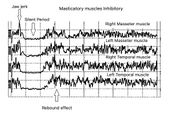

| 09:15, 4 June 2023 | Ortognatica Jaw jerk.jpeg (file) |  |

163 KB | Gianni | 3 |